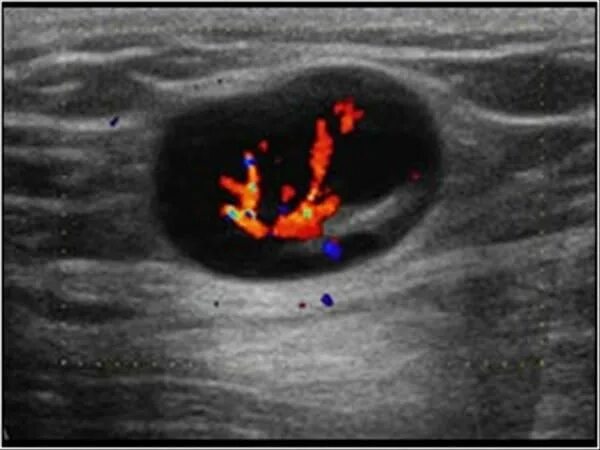

Метастазы в паховых лимфоузлах